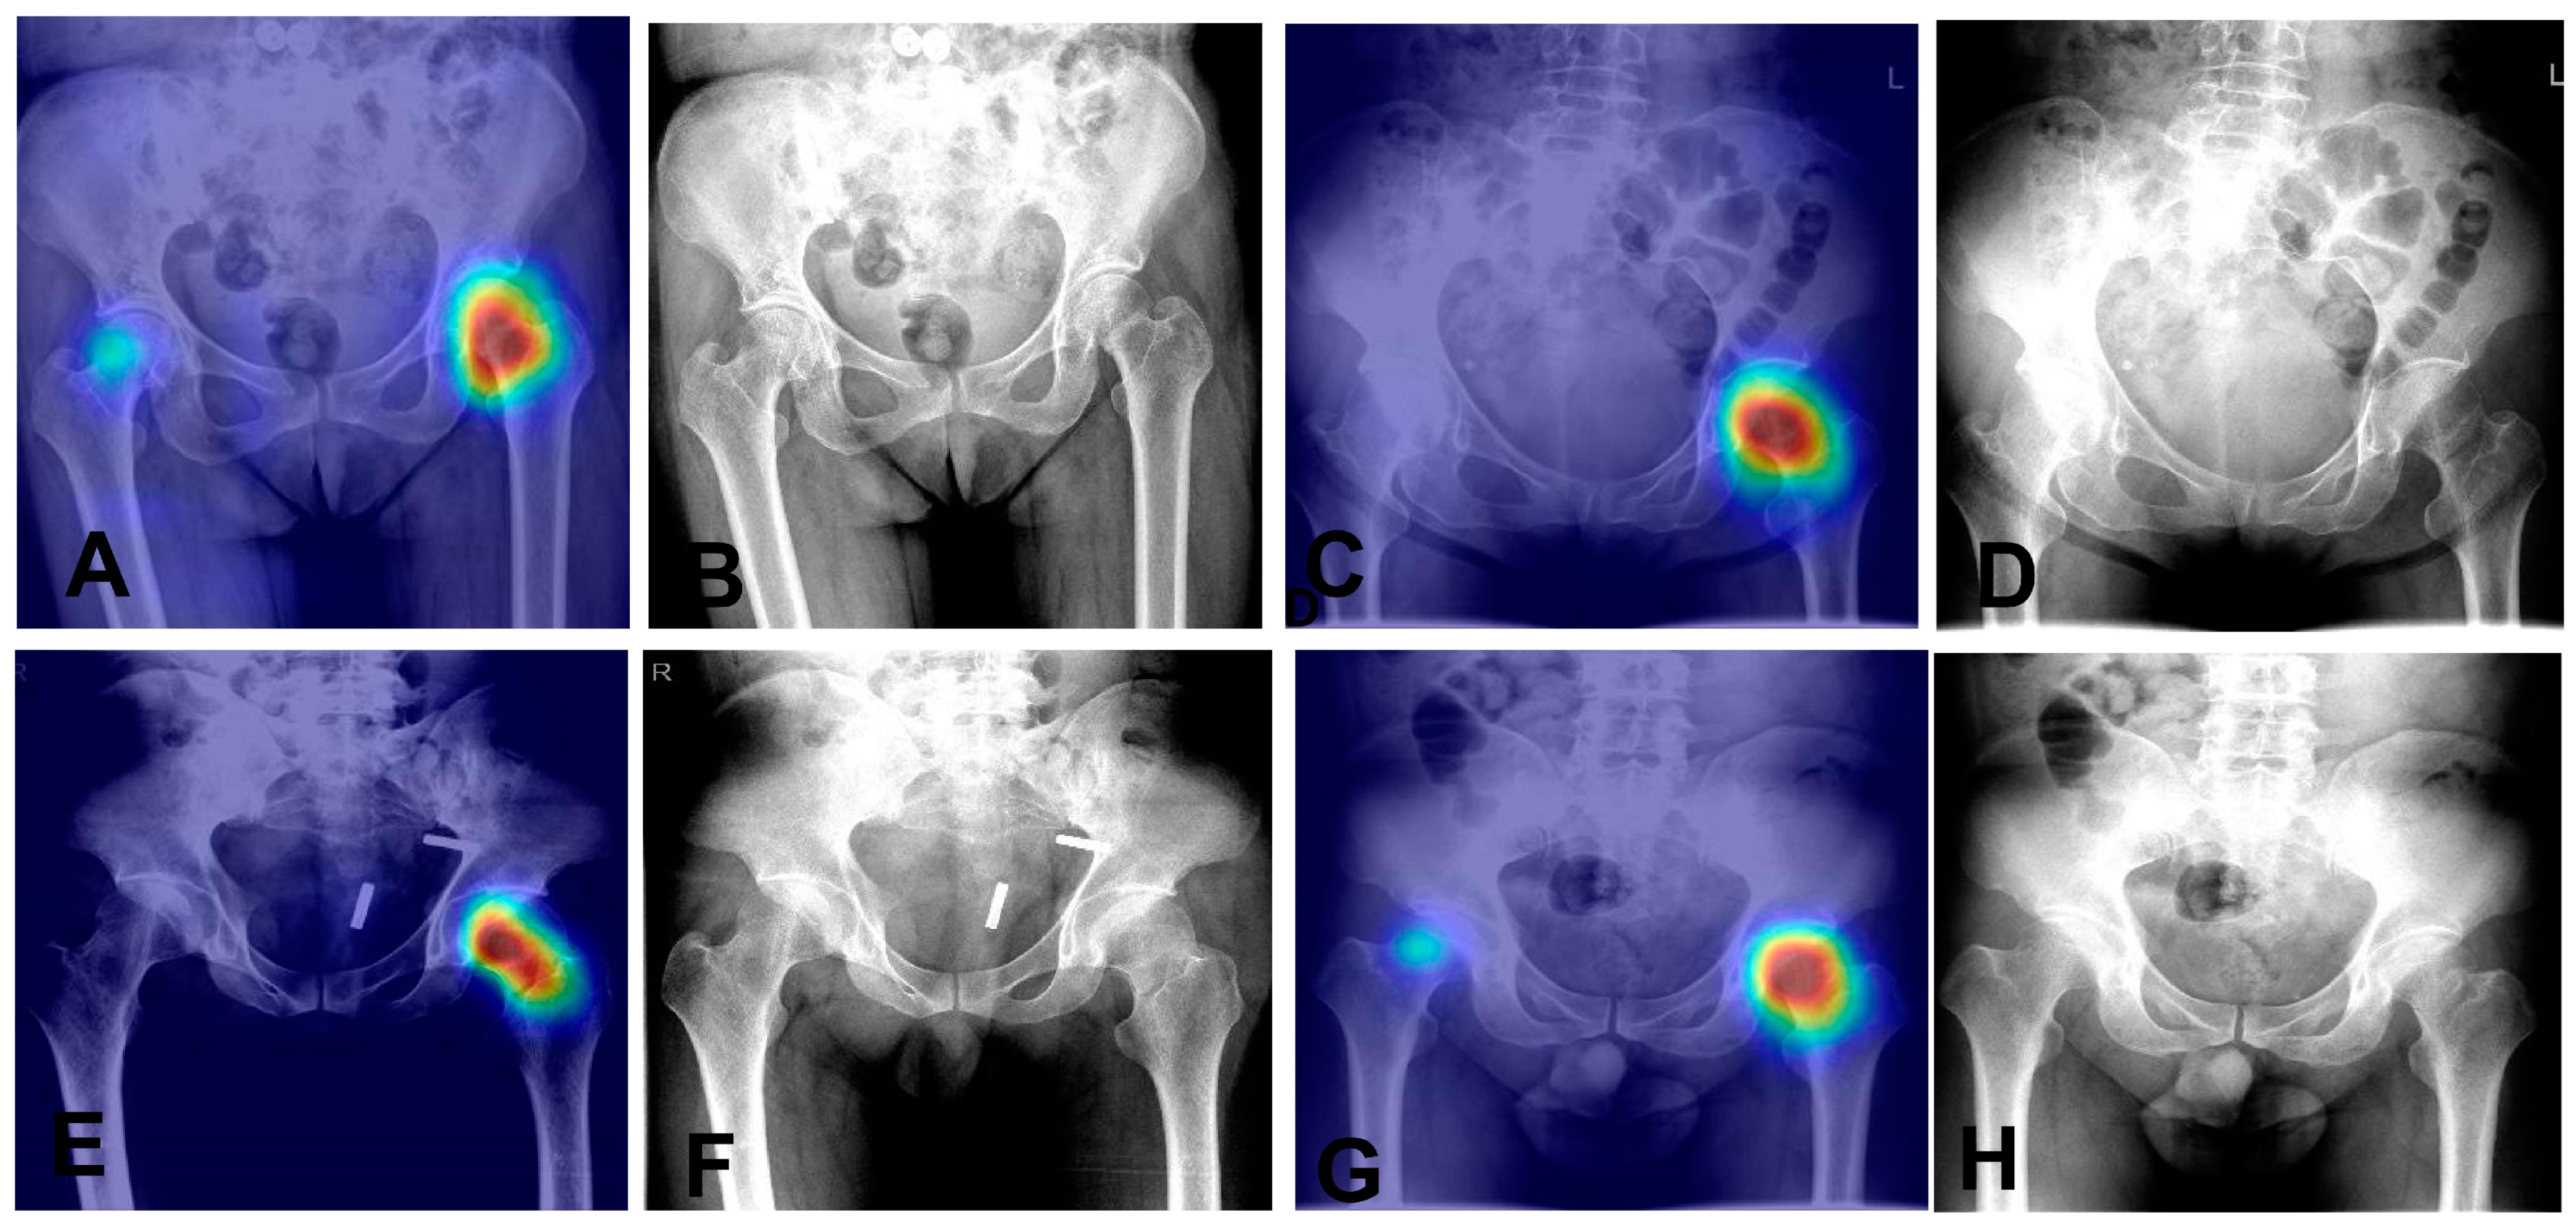

It has a sensitivity of 97.5% and a specificity of 95.1%, indicating it effectively recognizes both positive and negative cases. Overall, the model achieves an accuracy of 96.5%. The positive predictive value (PPV) is 96.5%, and the negative predictive value (NPV) is 96.6%, reflecting its reliability in predicting outcomes. The F1 score is 97.0%, highlighting the model’s balanced precision and recall. These results demonstrate the model’s high accuracy and reliability in diagnostics. We also utilized Grad—CAM maps for further analysis of our model’s behavior (as shown in Figure 5). The model is capable of accurately localizing the region of the nondisplaced femoral neck fracture.

Figure 5. Heatmaps and corresponding X-ray images of four nondisplaced femoral neck fracture cases. (A,B): Heatmap (A) and original X-ray (B) of Case 1. (C,D) Heatmap (C) and original X-ray (D) of Case 2. (E,F): Heatmap (E) and original X-ray (F) of Case 3. (G,H): Heatmap (G) and original X-ray (H) of Case 4.